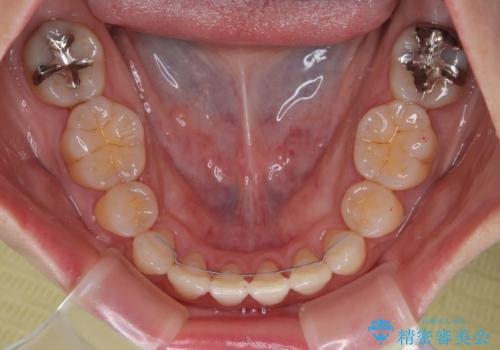

- 矯正装置

- 審美装置

- 前歯のデコボコと口元の突出感を気にして来院された患者様です。

上下前歯がくちばしのように突出していたため、上下左右の第一小臼歯4本を抜歯し、ワイヤー装置にて矯正治療を行うこととしました。

上顎骨に対して下顎骨がやや前方位に位置しているため、歯肉退縮を回避するために下顎前歯をあまり内側に移動させることができない状況でしたが、十分に口元の突出感を改善することができました。